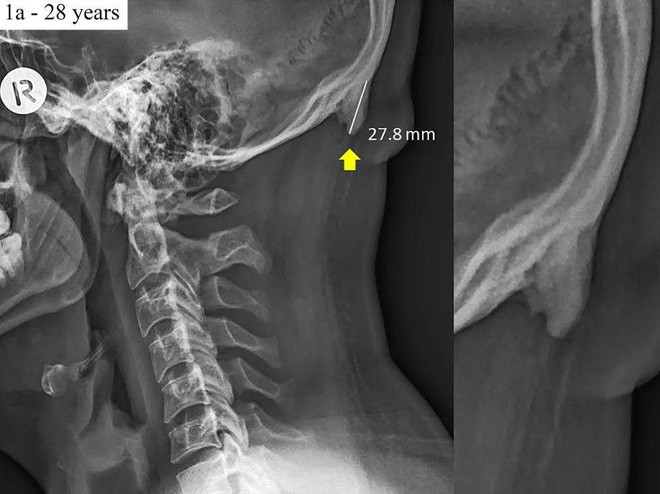

Ảnh chụp X-quang cho thấy gai nhô phía sau hộp sọ một người 28 tuổi

Trung bình, phần tăng trưởng thêm này dài khoảng 2,6 cm, nhưng cũng có những trường hợp cá biệt dài tới 3,1 cm. Nó được gọi với thuật ngữ khoa học là đáy gai nhô bên ngoài vùng chẩm (Enthesophytes or enlarged external occipital protuberance -EEOP)